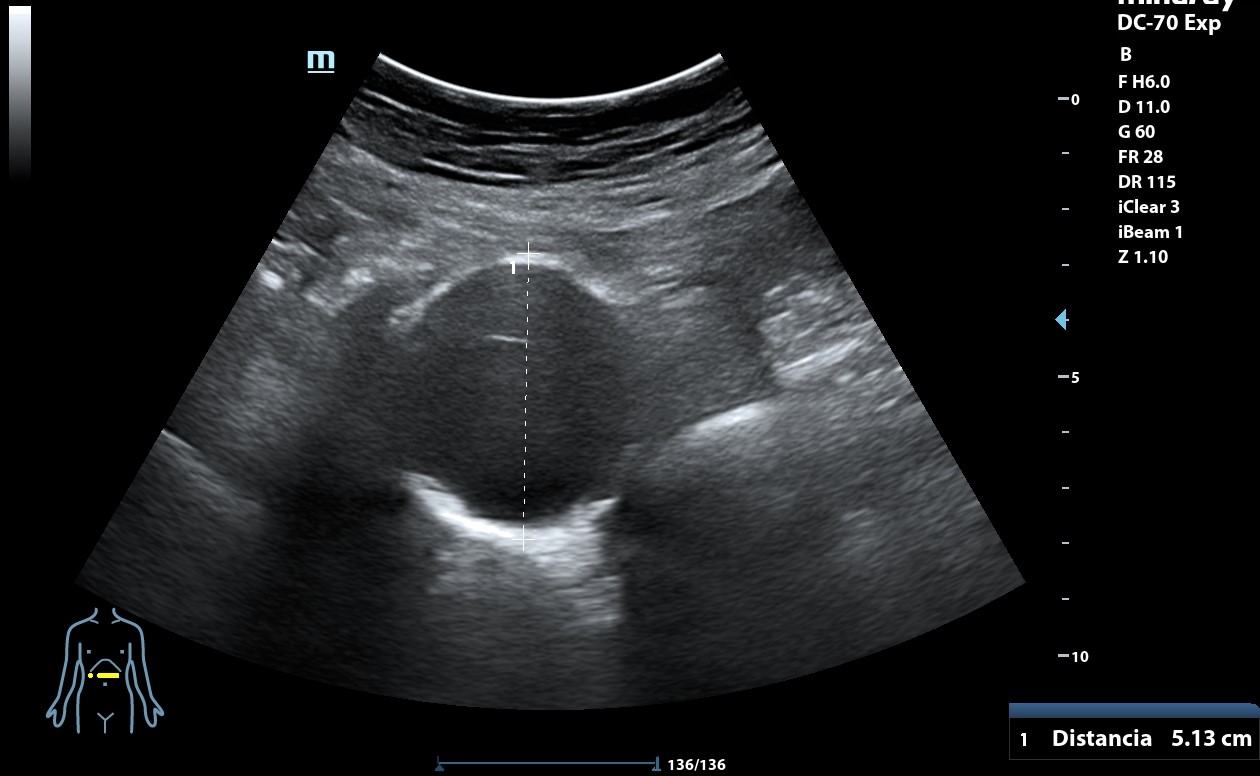

Ecografía clínica: arteria femoral dilatada con material hipoecoico heterogéneo en su pared lateral con un diámetro de 5,85 x 5,88 cm. Dilatación de aorta infrarrenal de 5,1 cm.

Diagnóstico: Aneurisma de arteria femoral derecha. aneurisma de aorta.

Informe TAC aorta: Dilatación aneurismática de la aorta abdominal infrarenal, de 5 x 5 x 6,4 cm, sin signos de complicación. Imagen sacular de la arteria femoral derecha compatible con pseudoaneurima, que asocia hematoma circundante, de al menos 8,6 x 7,8 x 8,8 cm con áreas de extravasación de contraste en fase arterial, sugestivas de sangrado activo de alto débito.